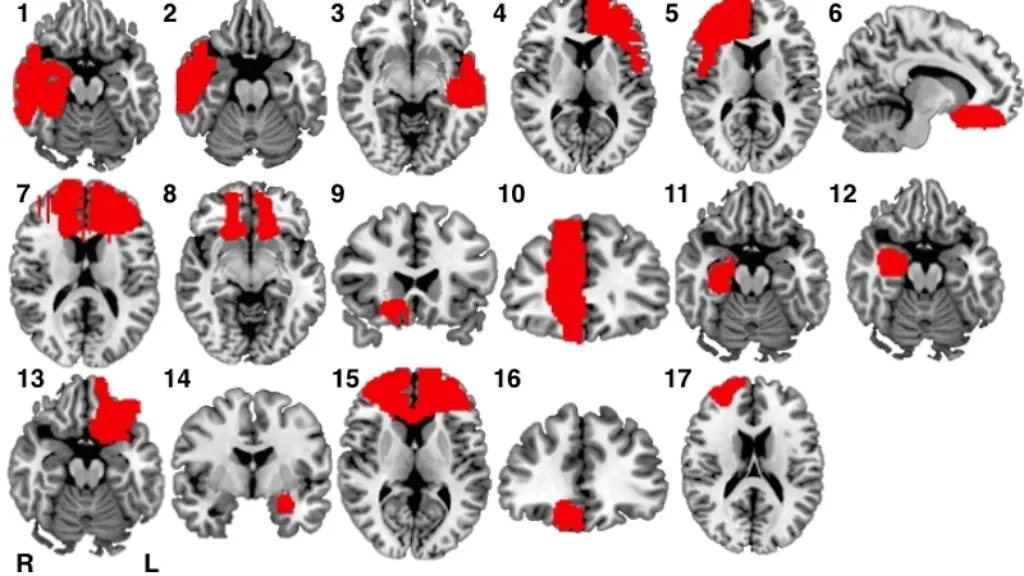

Eine US-Untersuchung zeigt, wie Verletzungen in verschiedenen Hirnregionen kriminelle Handlungen verursachen können. Die Neurologen um Michael Fox vom Beth Israel Deaconess Medical Center (BIDMC) in Boston, USA, analysierten 17 Betroffene und stellten fest: Alle verletzten Hirnregionen betrafen ein neuronales Netzwerk, das bei moralischen Entscheidungen aktiv ist. Das berichtet das Team in den "Proceedings" der US-Nationalen Akademie der Wissenschaften. Ein deutscher Experte betont, nun lasse sich ein Einfluss von Hirnschäden auf das Verhalten nicht mehr leugnen.

Das Team suchte in der Fachliteratur 17 Fälle, in denen Patienten nachweislich erst nach einer Hirnverletzung kriminelle Handlungen begangen hatten. In den Hirnscans fanden die Forscher sehr unterschiedliche Schädigungen; es gab keine einzelne Hirnregion, die in allen Fällen beschädigt war. Die Scans glichen die Wissenschaftler mit neuronalen Netzwerken ab, die in anderen Studien beschrieben waren. Solche Netzwerke haben Neurologen in den vergangenen Jahren mit bildgebenden Verfahren ermittelt, die Hirnaktivitäten bei bestimmten Aufgaben und auch im Ruhezustand zeigen.

Bei den Analysen entdeckte die Gruppe, dass alle geschädigten Hirnbereiche funktionell verbunden sind mit Regionen, die an moralischer Entscheidungsfindung und Annahmen über Bewusstseinsvorgänge bei anderen Menschen beteiligt sind. Nicht verknüpft waren die Verletzungen dagegen mit Regionen, die etwa an Mitgefühl mitwirken.